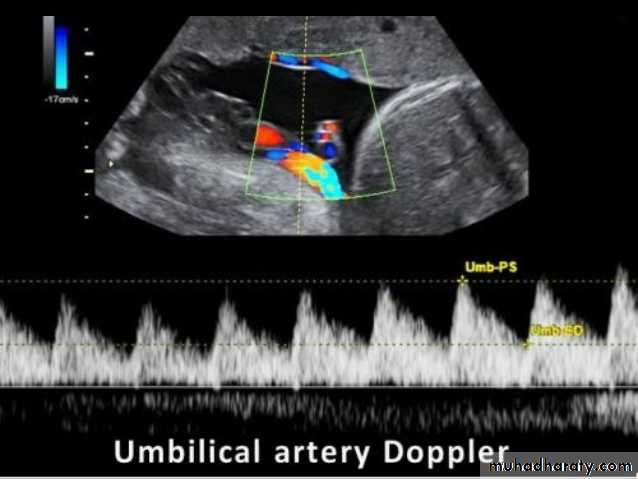

Ectopic pregnancy refers to the implantation of a fertilised ovum outside of the uterine cavity.

Radiographic features

Ultrasound

The ultrasound exam should be performed both transabdominally and transvaginally. The transabdominal component provides a wider overview of the abdomen, whereas a transvaginal scan is important for diagnostic sensitivity.

Positive sonographic findings include:

uterus

empty uterine cavity or no evidence of intrauterine pregnancy

Pseudo gestational sac or decidual cyst: may be seen in 10-20% of ectopic pregnancies

Direct visualization of the sac at the adenxia .